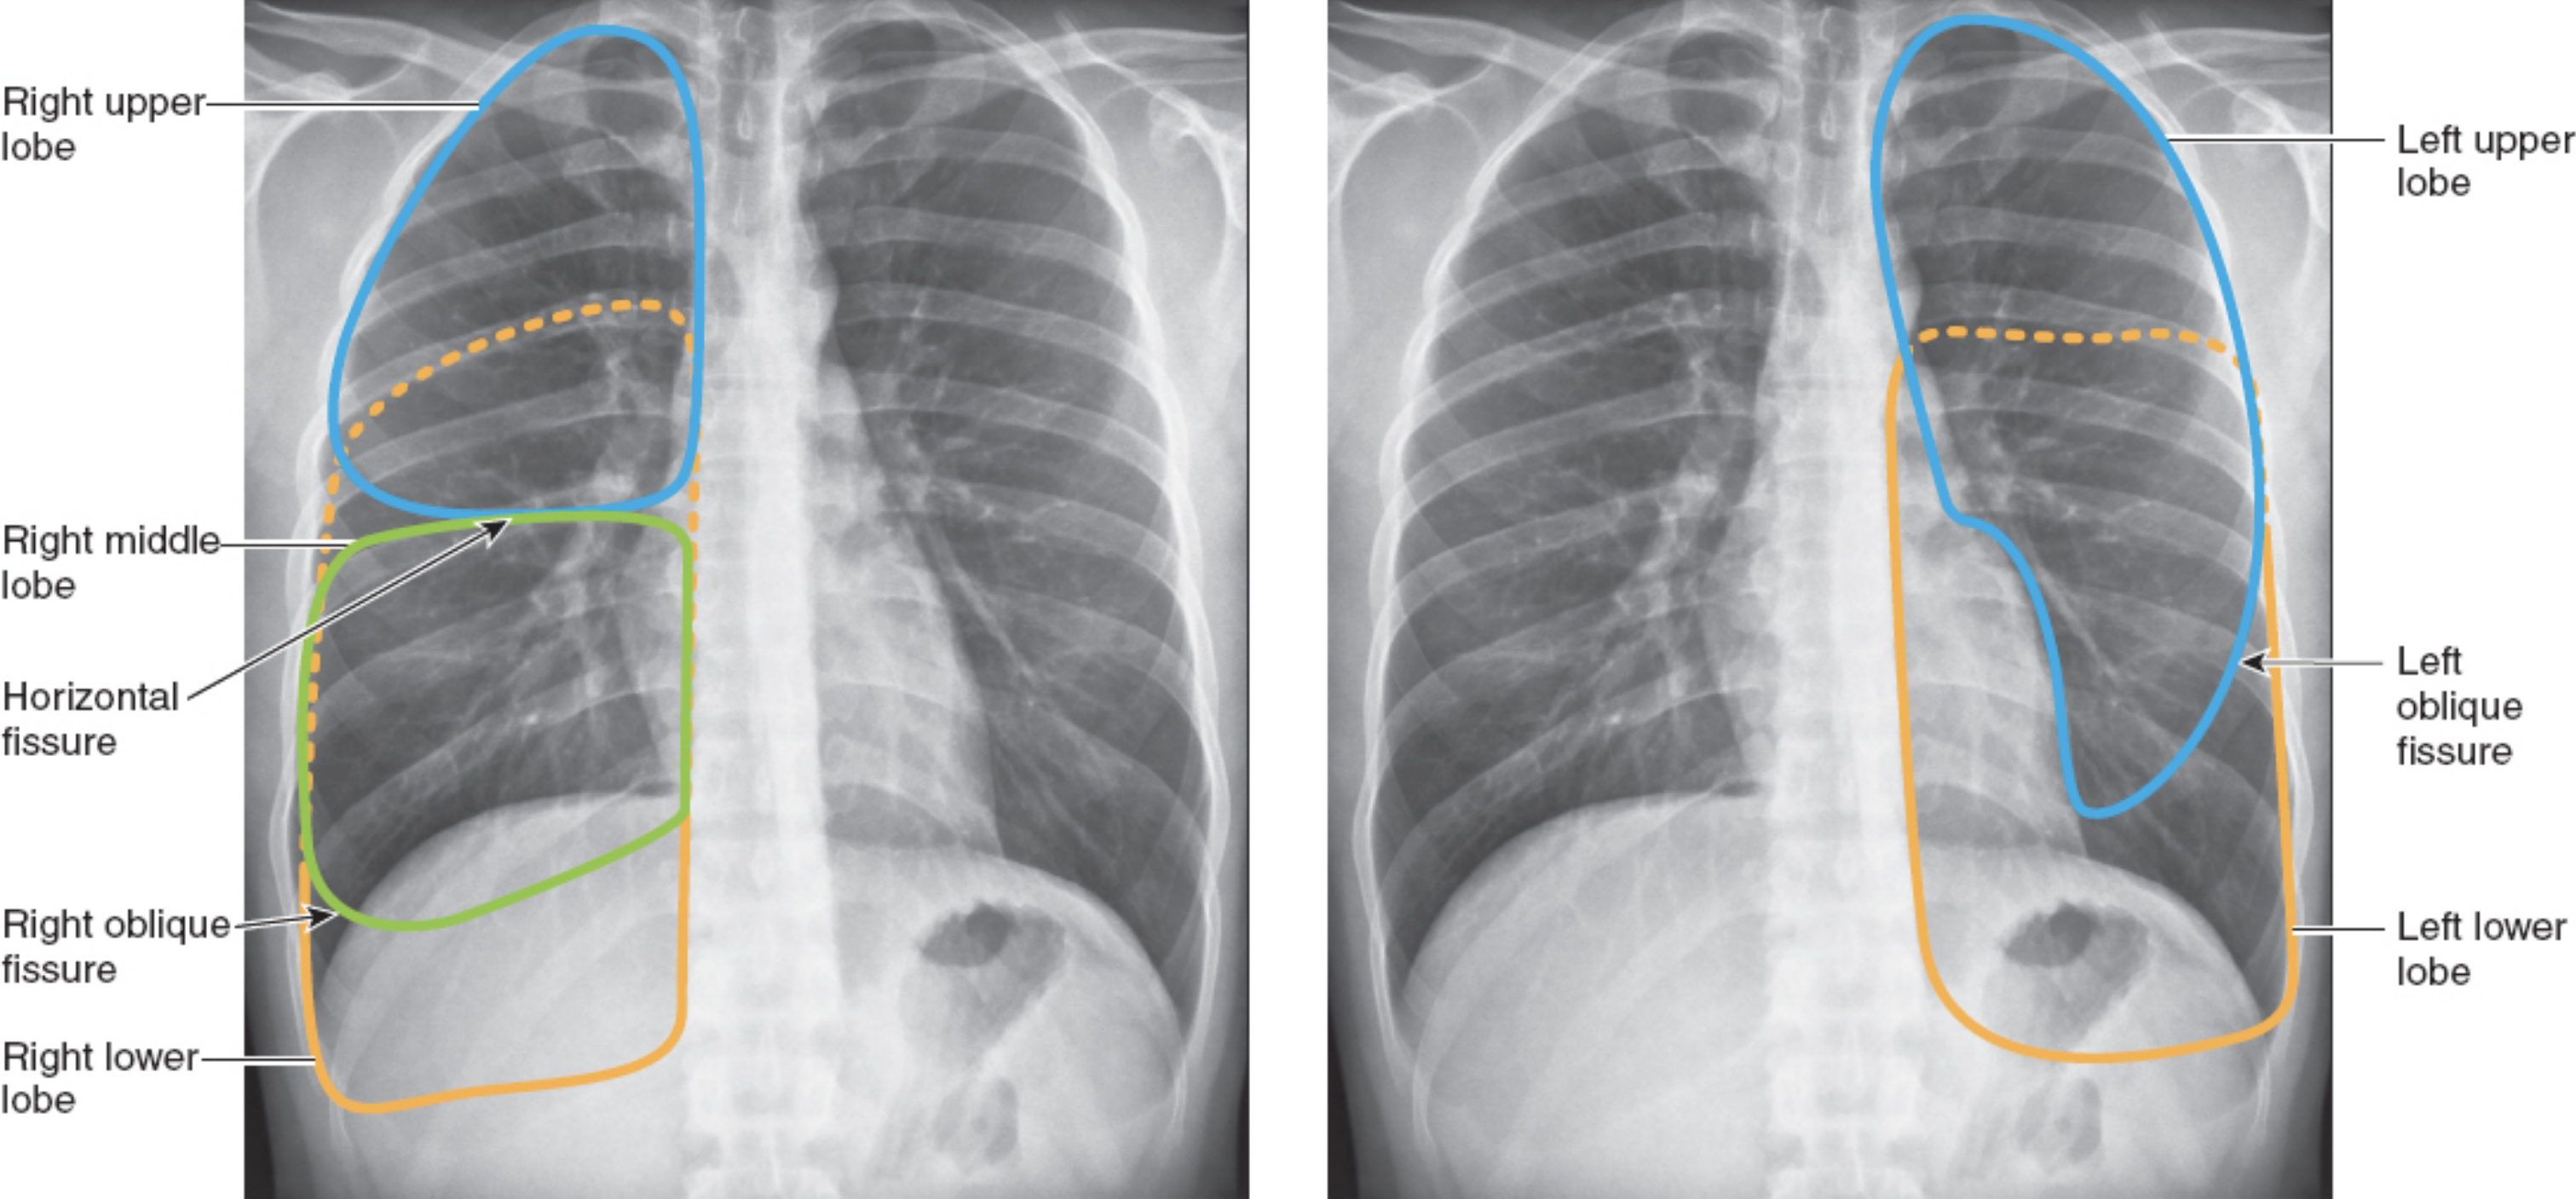

Understand lung anatomy (lobes, landmarks)

The left lung has no middle lobe

The anterior chest contains mostly upper and middle lobe with little lower lobe

The posterior chest contains almost all lower lobe